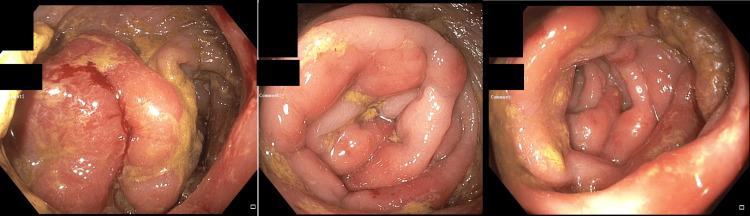

Syphilis is a sexually transmitted disease that impacts multiple organ systems and can mimic various diseases and is an extremely rare cause of proctitis in men who have sex with men and transgender females. We present a case of a 49-year-old transgender female with a medical history significant for diabetes mellitus and hyperlipidemia who presented to the emergency department with dull abdominal pain in the left upper and lower quadrants for two days. She had non-bloody, nonbilious emesis, 10-pound weight loss over 1 month, and constipation for 2 weeks. Laboratory results showed a cholestatic pattern. Computed tomography of the abdomen showed rectal wall thickening, multiple enlarged perirectal adenopathy, and mild inflammatory infiltration around the rectum suggesting superimposed proctitis. On colonoscopy, a possible rectal mass or severe proctitis with near complete obstruction was seen with initial pathology concerning for lymphoma or a rare type of colitis. The patient was empirically started on ceftriaxone and doxycycline leading to improvement in inflammation. Special stains requested were positive for Treponema pallidum confirming the diagnosis of syphilitic proctitis and highly suggestive syphilitic hepatitis. Few cases of syphilitic proctitis imitating rectal malignancy and syphilitic hepatitis have been reported. Syphilis requires exclusion as well as confirmation of spirochetes for high-risk populations with special staining. It is important to diagnose syphilis in special populations that are at high risk of contraction.

梅毒是一种性传播疾病,可影响多个器官系统,能模仿多种疾病,是男男性行为者和变性女性中直肠炎极为罕见的病因。我们报告一例49岁变性女性病例,其有糖尿病和高脂血症病史,因左上腹和左下腹钝痛两天就诊于急诊科。她有非血性、非胆汁性呕吐,1个月内体重减轻10磅,便秘2周。实验室检查结果显示胆汁淤积模式。腹部计算机断层扫描显示直肠壁增厚、多个直肠周围淋巴结肿大以及直肠周围轻度炎症浸润,提示合并直肠炎。结肠镜检查时,可见一个可能的直肠肿物或严重直肠炎伴近乎完全梗阻,初步病理检查怀疑为淋巴瘤或一种罕见类型的结肠炎。患者经验性使用头孢曲松和多西环素治疗后炎症有所改善。所要求的特殊染色显示苍白螺旋体阳性,确诊为梅毒性直肠炎,并高度提示梅毒性肝炎。很少有梅毒性直肠炎模仿直肠恶性肿瘤及梅毒性肝炎的病例报道。对于高危人群需通过特殊染色排除并确认螺旋体以诊断梅毒。在有高感染风险的特殊人群中诊断梅毒很重要。